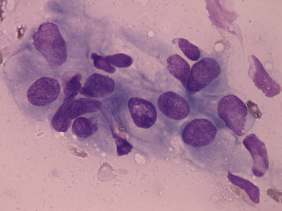

Cytology was performed from the discrete lesion in the left lobe and resulted in Hashimoto's thyroiditis.

Our final diagnosis was hypothyroidism caused by Hashimoto's thyroiditis. A benign lesion in the left lobe.

Histopathology disclosed Hashimoto's thyroiditis without any nodule.